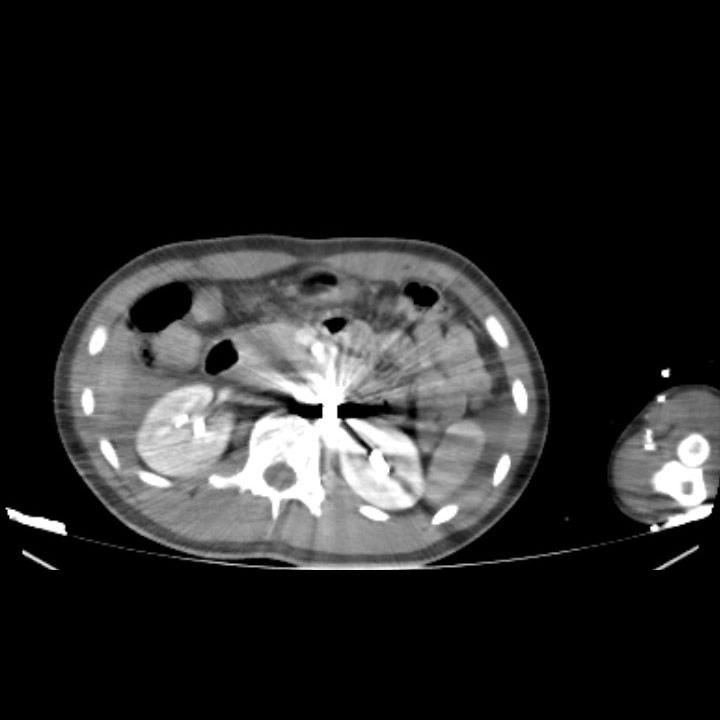

Masculino 17 años HAF